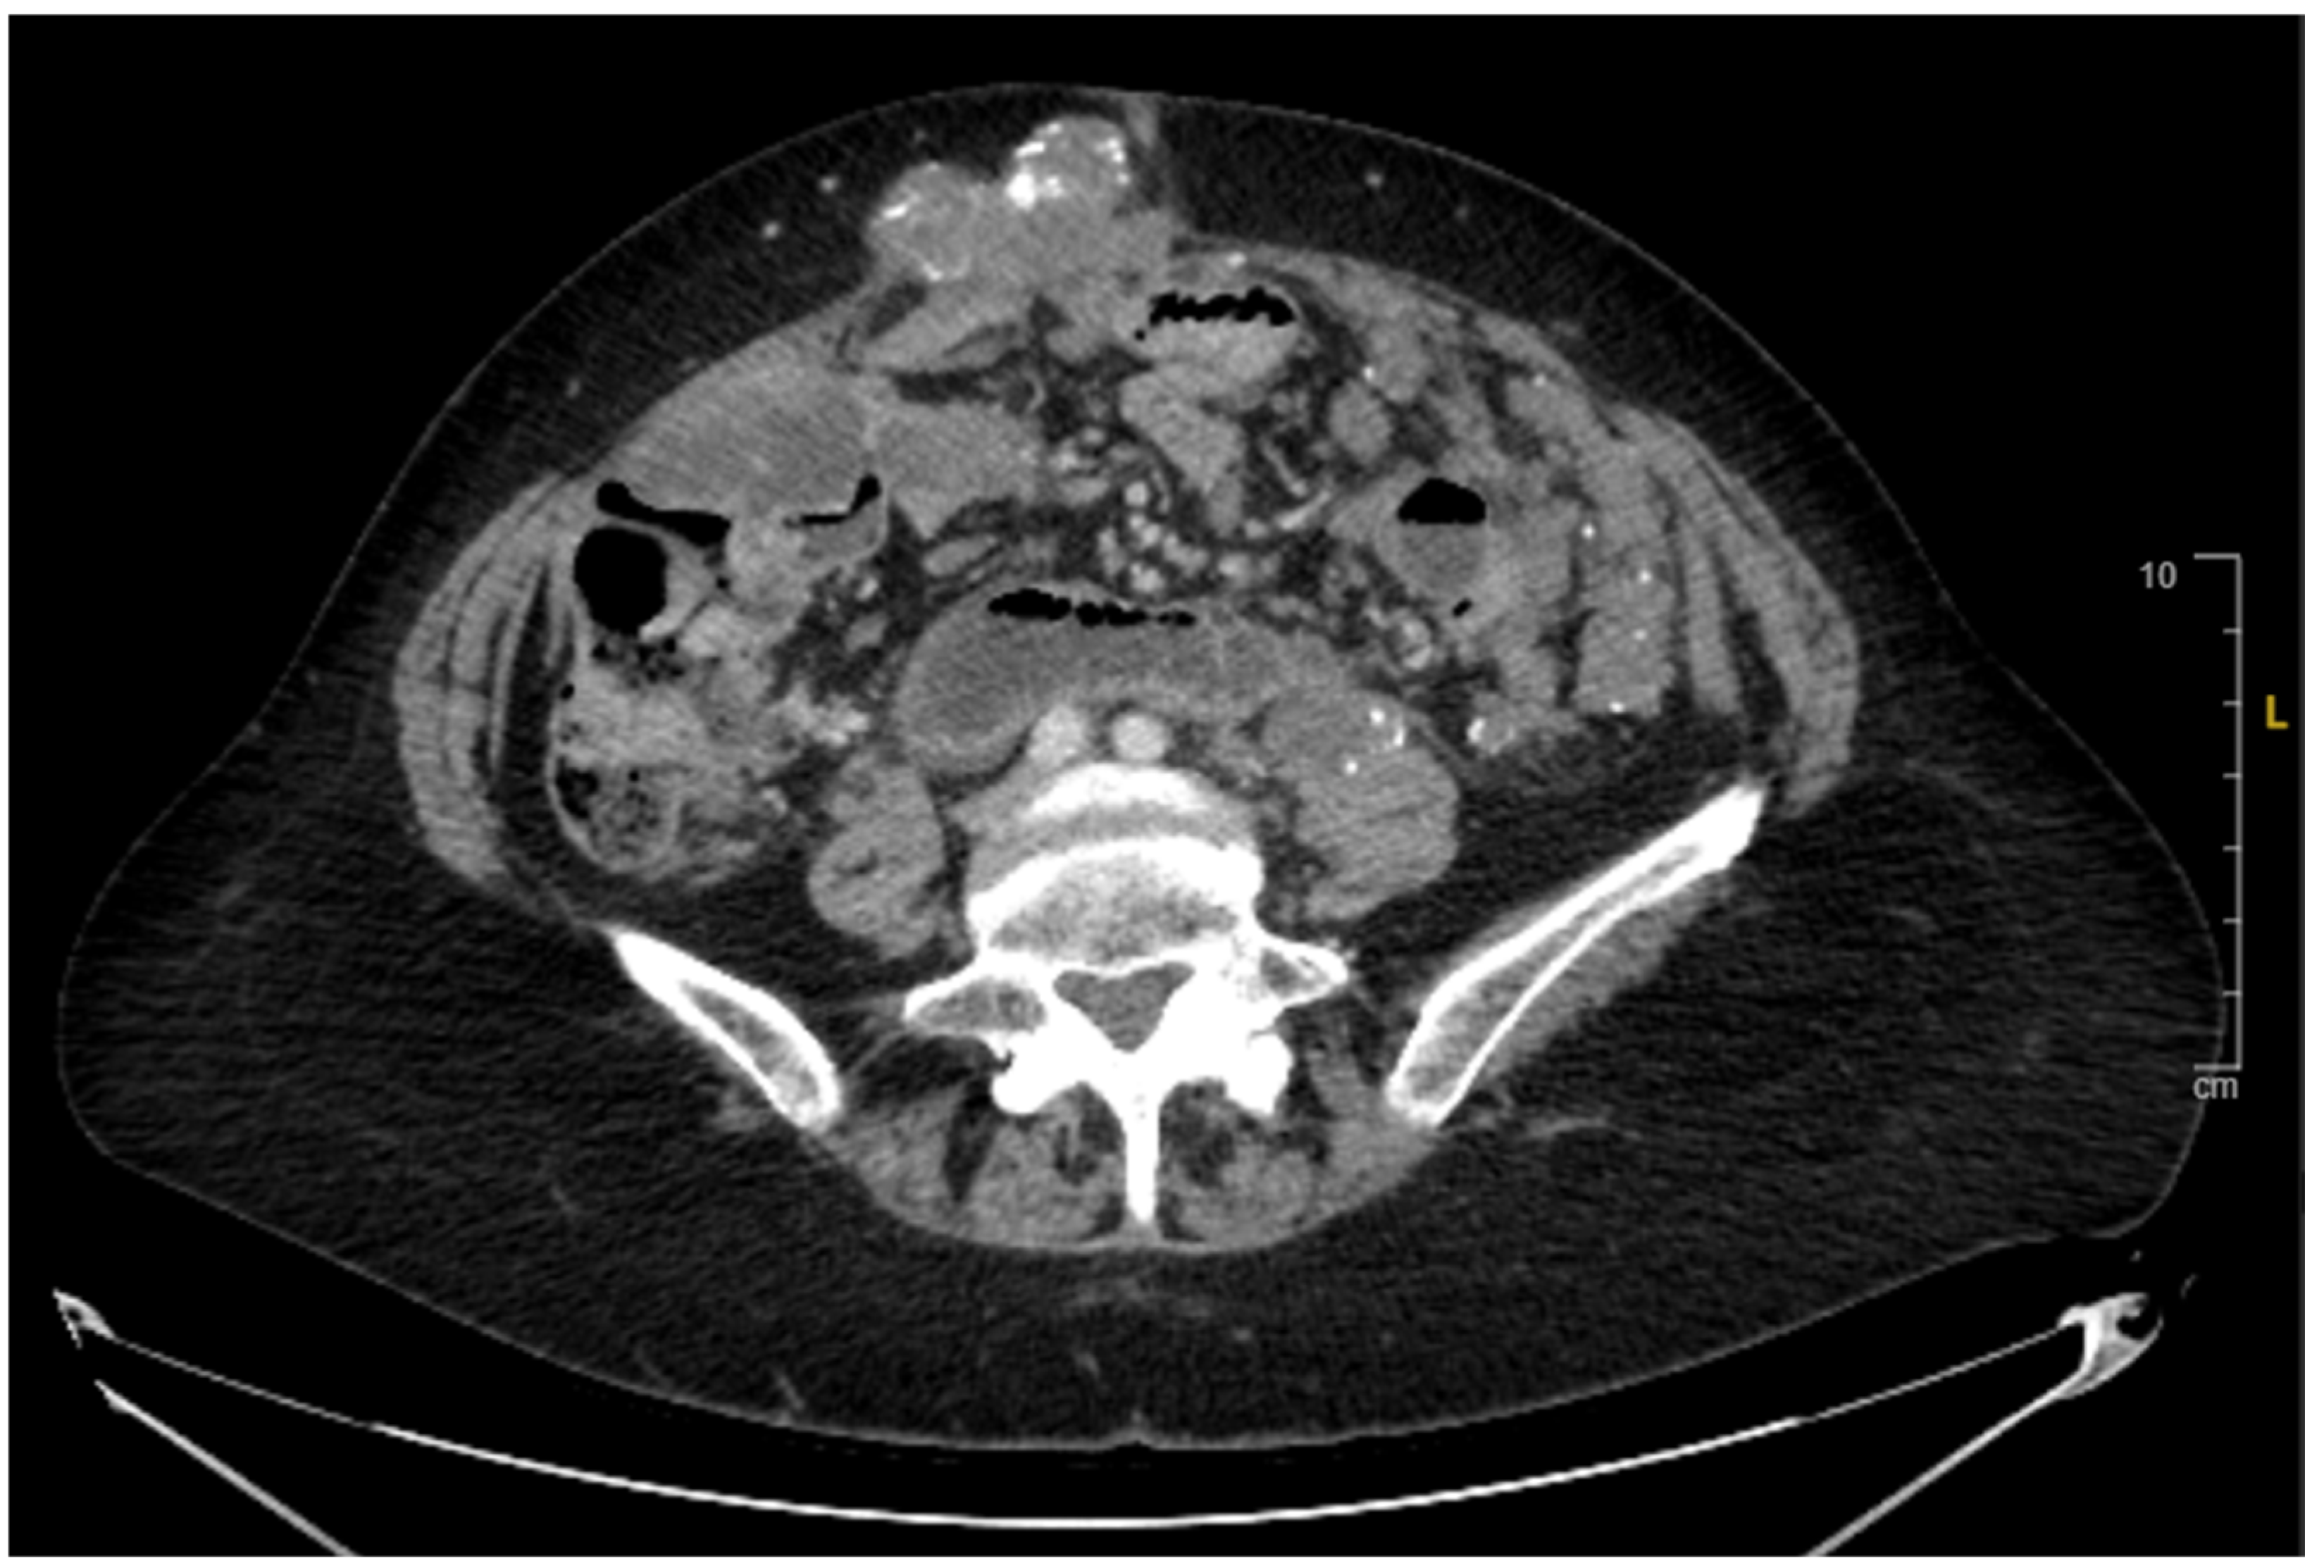

2. Case Presentation